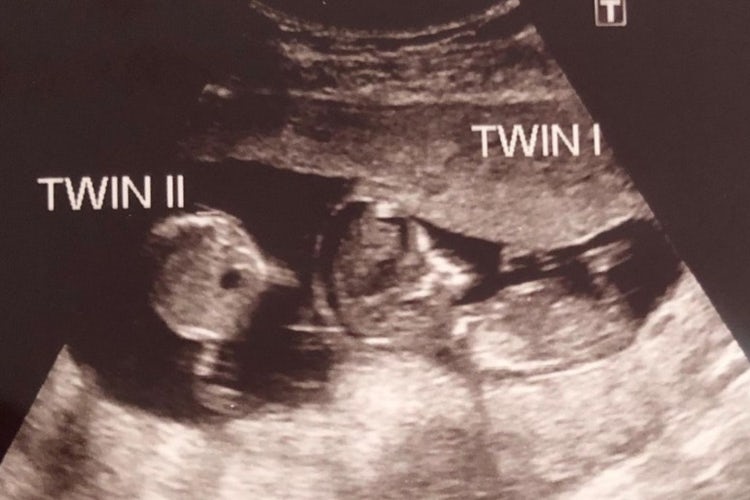

Takto vypadal ultrazvukový snímek neobvyklých dvojčat.